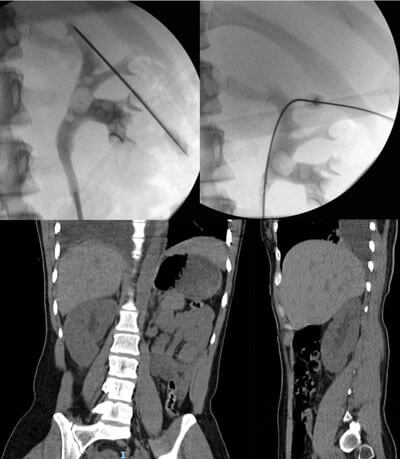

Figure 1: Right-sided hydrothorax post-supra 12th access for PCNL.

Pleural compromise

This is a rare complication but one that is important to identify early (Figure 1). The risk of injury increases for punctures that are supracostal especially those that are medial. Identification requires a degree of clinical suspicion; intraoperative signs include elevated pressures on ventilation and hypoxia. However, symptoms of respiratory compromise and pain do not usually declare themselves until the nephrostomy tube is removed (due to the tamponade effect of tube against pleura). Treatment is a rapid chest CT and urgent insertion of a chest drain.

Ultrasound-guided puncture allows assessment of the pleura prior to puncture and shows movement in real-time. Despite this, supracostal access has a 10-15% risk of intrathoracic complications, compared to 1.5-4.5% with subcostal access [27]. Whilst a coiled nephrostomy is often enough to drain fluid and allow the pleura to heal, in cases where there is spillage of debris or significant empyema a formal chest drain may be required.

Figure 2: Post-PCNL bleed into retroperitoneum.

Postoperative bleeding (Figure 2) can be usually resolved by a short period of nephrostomy clamping (10-15 minutes), especially if arising from venous vasculature. However, it is prudent to have a high clinical incidence of suspicion in such cases and proceed to renal angiography with angioembolisation. The postoperative transfusion rate varies widely in the literature, with the British Association of Urological Surgeons quoting the national average as 2.1% [29].

Whilst initially it might be reassuring, the absence of any blood-stained urine in the urethral catheter may indicate ipsilateral ureteric obstruction (either from a stone fragment, ureteric oedema or a blood clot) as the clear urine seen in the bladder represents normal urine from the contralateral kidney. Within this scenario, persistent and worsening haematuria through the nephrostomy is an indicator of clot-colic, for which additional vigilance for bleeding is needed. In any of these situations, imaging (by CT KUB, nephrostogram or CT angiogram as appropriate) will identify the level and cause of obstruction and allow onward management as required, including the opportunity to deploy an antegrade stent via the nephrostomy tract (Figure 3).

Figure 3: Pain on clamping nephrostomy with ensuing extravasation secondary

to distal obstruction followed by interval nephrostogram after antegrade stent.